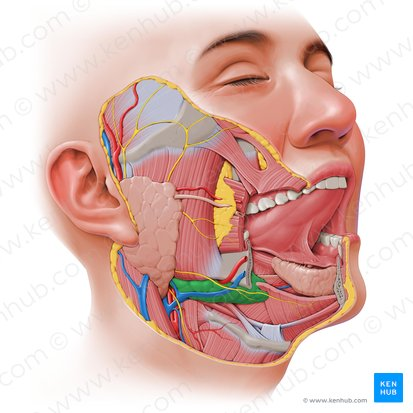

Submandibular Gland

One of the major salivary glands, located beneath the mandible. It produces a mixed serous and mucous saliva, contributing significantly to total salivary volume.

Submandibular Duct

The duct that carries saliva from the submandibular gland to the floor of the mouth, opening at the sublingual papilla under the tongue.